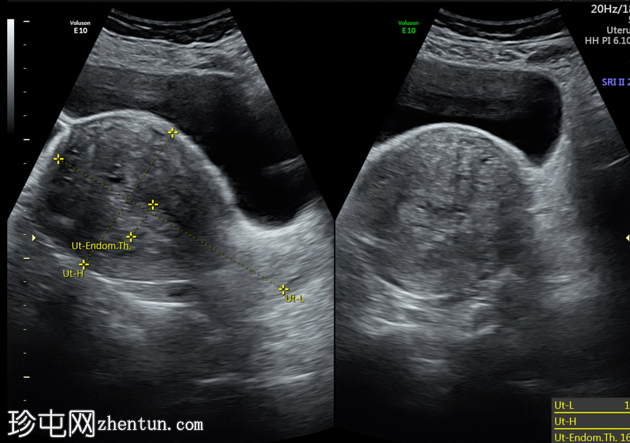

超声检查

子宫增大,肌层弥漫性增厚。移行区厚度约2.5厘米,呈不均匀回声,可见细小强回声条纹、微小肌层囊肿、轻微百叶窗样改变,以及轻度多普勒血流信号增强。

子宫增大,交界区弥漫性增厚,厚度约2.5 cm,边界模糊,在T1加权像和T2加权像上均可见无数点状高信号灶,提示出血灶。

盆腔影像学检查(超声或MRI)通常显示局灶性或弥漫性、常不对称的子宫肌层增厚,并伴有异质性影像。

我们报告一例50岁女性患者,其超声和MRI影像均表现出弥漫性子宫腺肌症的特征性表现。